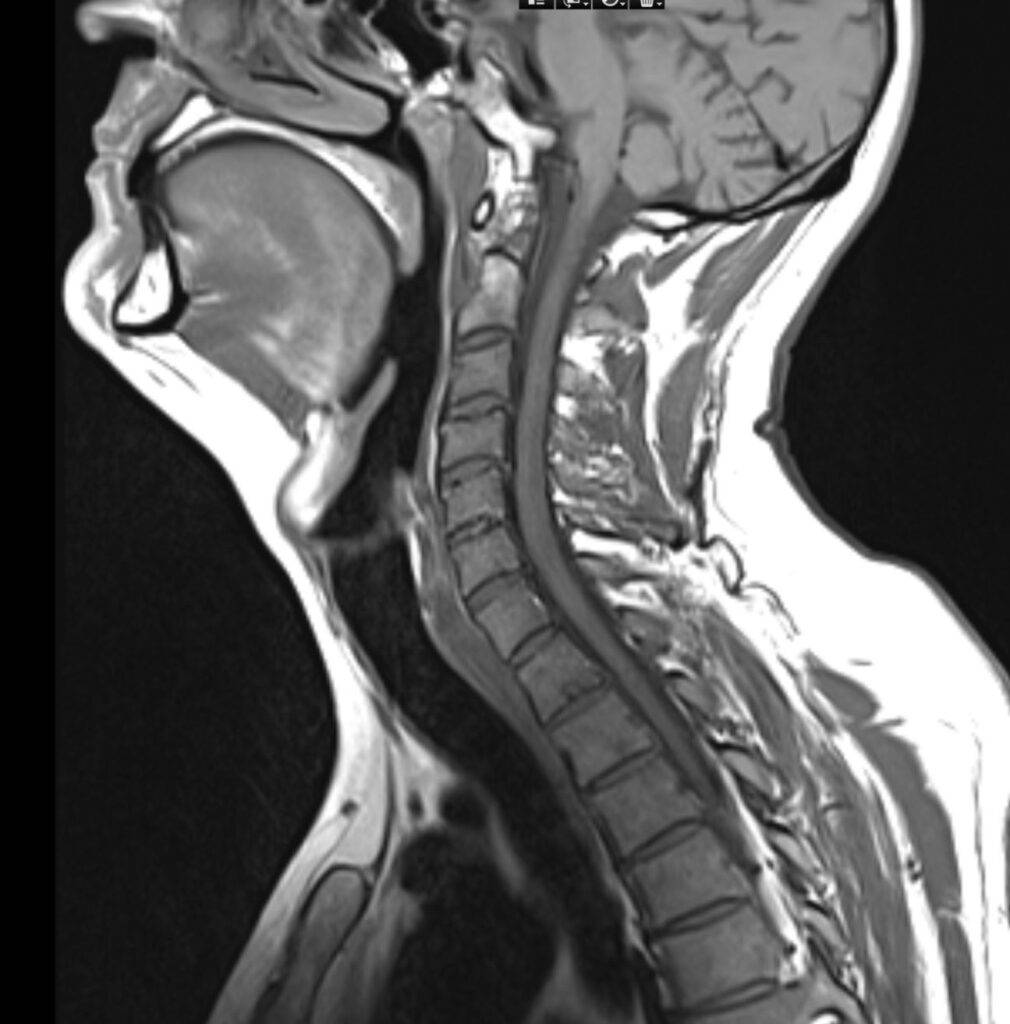

Eine Magnetresonanztomographie des Kopfes, kurz die MRT Kopf genannt, ist ein medizinisch bildgebendes Verfahren. Die MRT Kopf Untersuchung stellt mit Hilfe von Magnetfeldern und Radiowellen insbesondere unser Gehirn, Ohr, Nase und Nasennebenhöhlen, Augen, Kiefer, sowie genaue Strukturen detailliert dar. Vor allem bei diffusen oder langanhaltenden Kopfschmerzen kann eine MRT aufschlussreich sein. Vor allem ermöglicht eine Kopf MRT Einblicke in verschiedene neurologische Erkrankungen.

Eine Kopf MRT liefert Ärzte und Radiologen detaillierte Bilder. Zu sehen sind das Gehirn, Schädelknochen, Blutgefäße und anderer umgebende Gewebe im Kopfbereich.

„MRT Kopf“ bezieht sich allgemein auf die Untersuchung des gesamten Kopfbereichs, einschließlich Gehirn, Schädel und umliegender Strukturen. „MRT Schädel“ sowie „MRT Gehirn“ beziehen sich auf dieselbe Untersuchung. Unterschieden wird im untersuchenden Bereich: Gehirn, Schädelknochen, Nase und Nasennebenhöhlen, Ohr oder Kiefer.